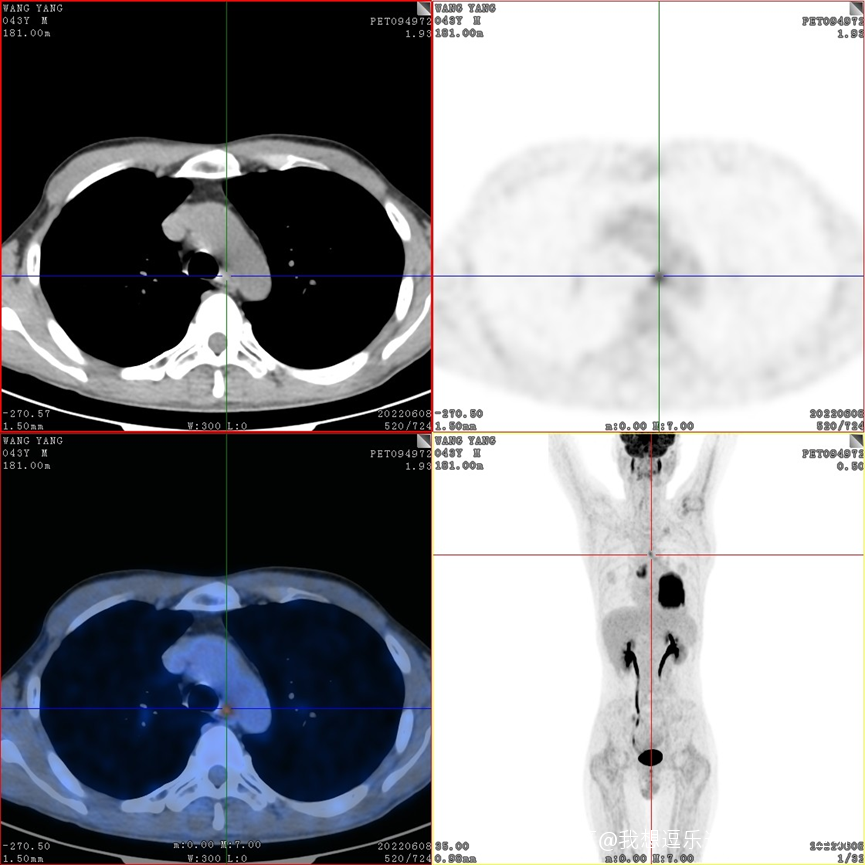

同時行PET-CT檢查,發現同側縱隔淋巴結出現了轉移(N2),所幸沒有遠處轉移(M0)。臨牀分期為cT4N2M0,IIIB期,暫時不考慮手術。

PET-CT提示同側縱隔淋巴結轉移

我們進行了氣管鏡檢查,取了病理、做了基因檢測,考慮先行新輔助治療,將來再評估能否手術。